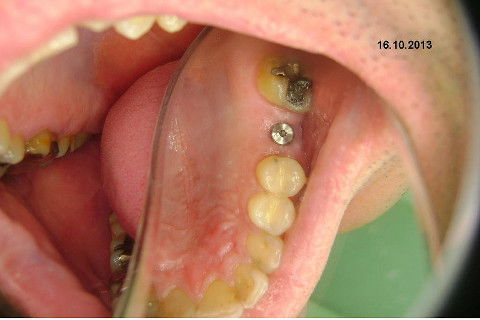

Instalação de um implante em região do 26. Utilizamos um implante cone morse Alvim Neodent 4.3 X 11,5. Foi uma cirurgia muito rápída e minimamente traumática, sem retalho e sutura.